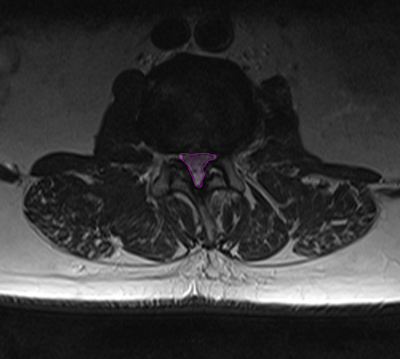

SpinalStenosis2 ForamenStenosis

Αριστερά: Στένωση οσφυϊκού σπονδυλικού σωλήνα. Δεξιά:Φυσιολογικό νευρικό τρήμα στην κορυφή (πράσινο) με ελεύθερο νεύρο στο κέντρο (μπλέ περίγραμμα). Στενό τρήμα (κυανό βέλος) και ουσιαστικά κλειστό τρήμα,το οποίο εμπεριέχει μόνο το πιεσμένο νεύρο (πράσινο βέλος). Τεμάχιο δισκοκήλης εντός του τρήματος (κόκκινο περίγραμμα).